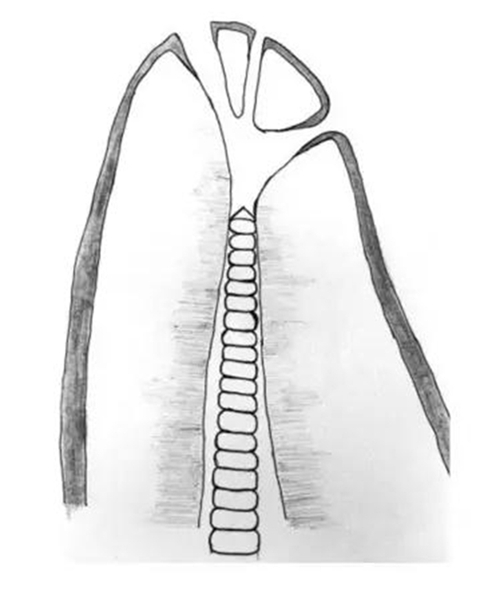

根尖狹窄的分類 (Dummer et al. 1984),黑色尖頭指的是根管最狹窄處

Dummer et al. (1984) 對270個離體牙進行縱向切割 (longitudinal sectioning) ,并在顯微鏡下觀察,發(fā)現(xiàn)傳統(tǒng)的根尖狹窄(上圖 Type A)只占46%;有30%的牙齒根管并沒有明顯最狹窄處,AC基本就在根尖開口的位置 (Type B);19%是多個狹窄區(qū) (Type C);最后還有5%的情況是平衡的狹窄段 (Type D)。

作者還測量了由牙根尖端(apex)到根管狹窄(constriction)的距離(A-C),平均為0.89mm,基本符合臨床選擇的距影像學尖端0.5-1mm的做法,但這樣的工作長度對于Type B來說卻屬于根管欠預備(under preparation)。